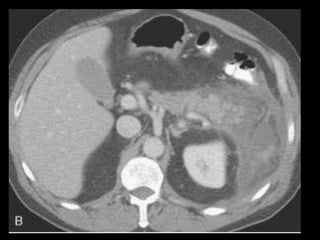

PANCREATITE AGUDA GRAVE

A administração de contraste IV é essencial,

especialmente em pacientes com PA grave, para

visualizar o pâncreas, diferenciar a glândula de

coleções líquidas adjacentes e do tecido

inflamatório peripancreático e demonstrar a

necrose pancreática.

Áreas focais ou difusas de realce diminuídas ou

ausente à TC contrastada dinâmica constituem

áreas de isquemia ou necrose.

TC tem precisão geral de 87% com S e E de 100%

para necrose extensa e 50% com áreas menores.